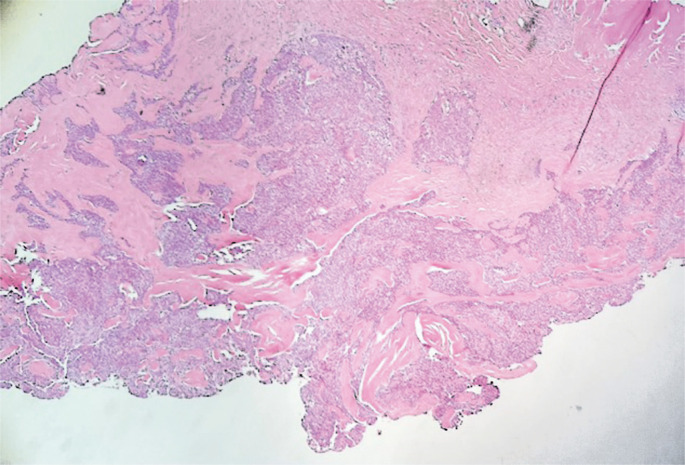

The etiologies of vulvar nodules range from infectious to neoplastic. Owing to the wide spectrum of vulvar diseases, clinical differentiation of the lesions is crucial for adequate diagnosis and management. A 46-year-old patient presented with a nodular lesion in the vulvar region that had been growing slowly for 10 years. Gynecological examination revealed the presence of a solid nodular lesion measuring approximately 3 cm in the middle third of the right labia majora without phlogistic signs or secretion discharge. The lesion was excised and an anatomopathological study revealed a nodular hidradenoma. Nodular hidradenoma is a rare benign neoplasm of the apocrine glands that mainly affects women between 30 and 60 years of age. Although generally asymptomatic, some symptoms have been described, such as itching, pain, ulceration, or secretory discharge. The diagnosis was made by an anatomopathological study, and treatment consisted of total excision of the lesion without the need to enlarge the margin. During the investigation, malignant lesions such as liposarcoma of the vulvar region and non-melanoma skin cancers were excluded. Differential diagnosis is important because it requires a more invasive approach and surgical margins. This report aimed to expand the knowledge of the diagnosis of vulvar hidradenoma to exclude the possibility of malignant neoplasia while caring for vulvar nodules, thereby allowing proper management of the case.